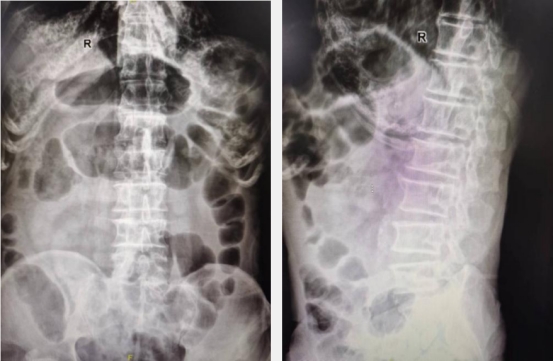

通过系统科学的围手术期管理,老人各项指标均达到手术要求。在麻醉科医师的严密生命体征监护下,王岩松带领程道林仅用时30分钟,利用X线反复透视定位,通过直径仅2.5mm的穿刺针,精准地向病椎中注入骨水泥,并严格控制注入量避免了骨水泥渗漏,手术结束后患者腰部仅有2个芝麻大小的针孔,无需缝合。术中患者未出现任何不适,术中及术后X线影像学检查证明骨水泥灌注满意,椎体已恢复高度。

术后复查X线可见骨水泥填充满意无渗漏,椎体高度已恢复